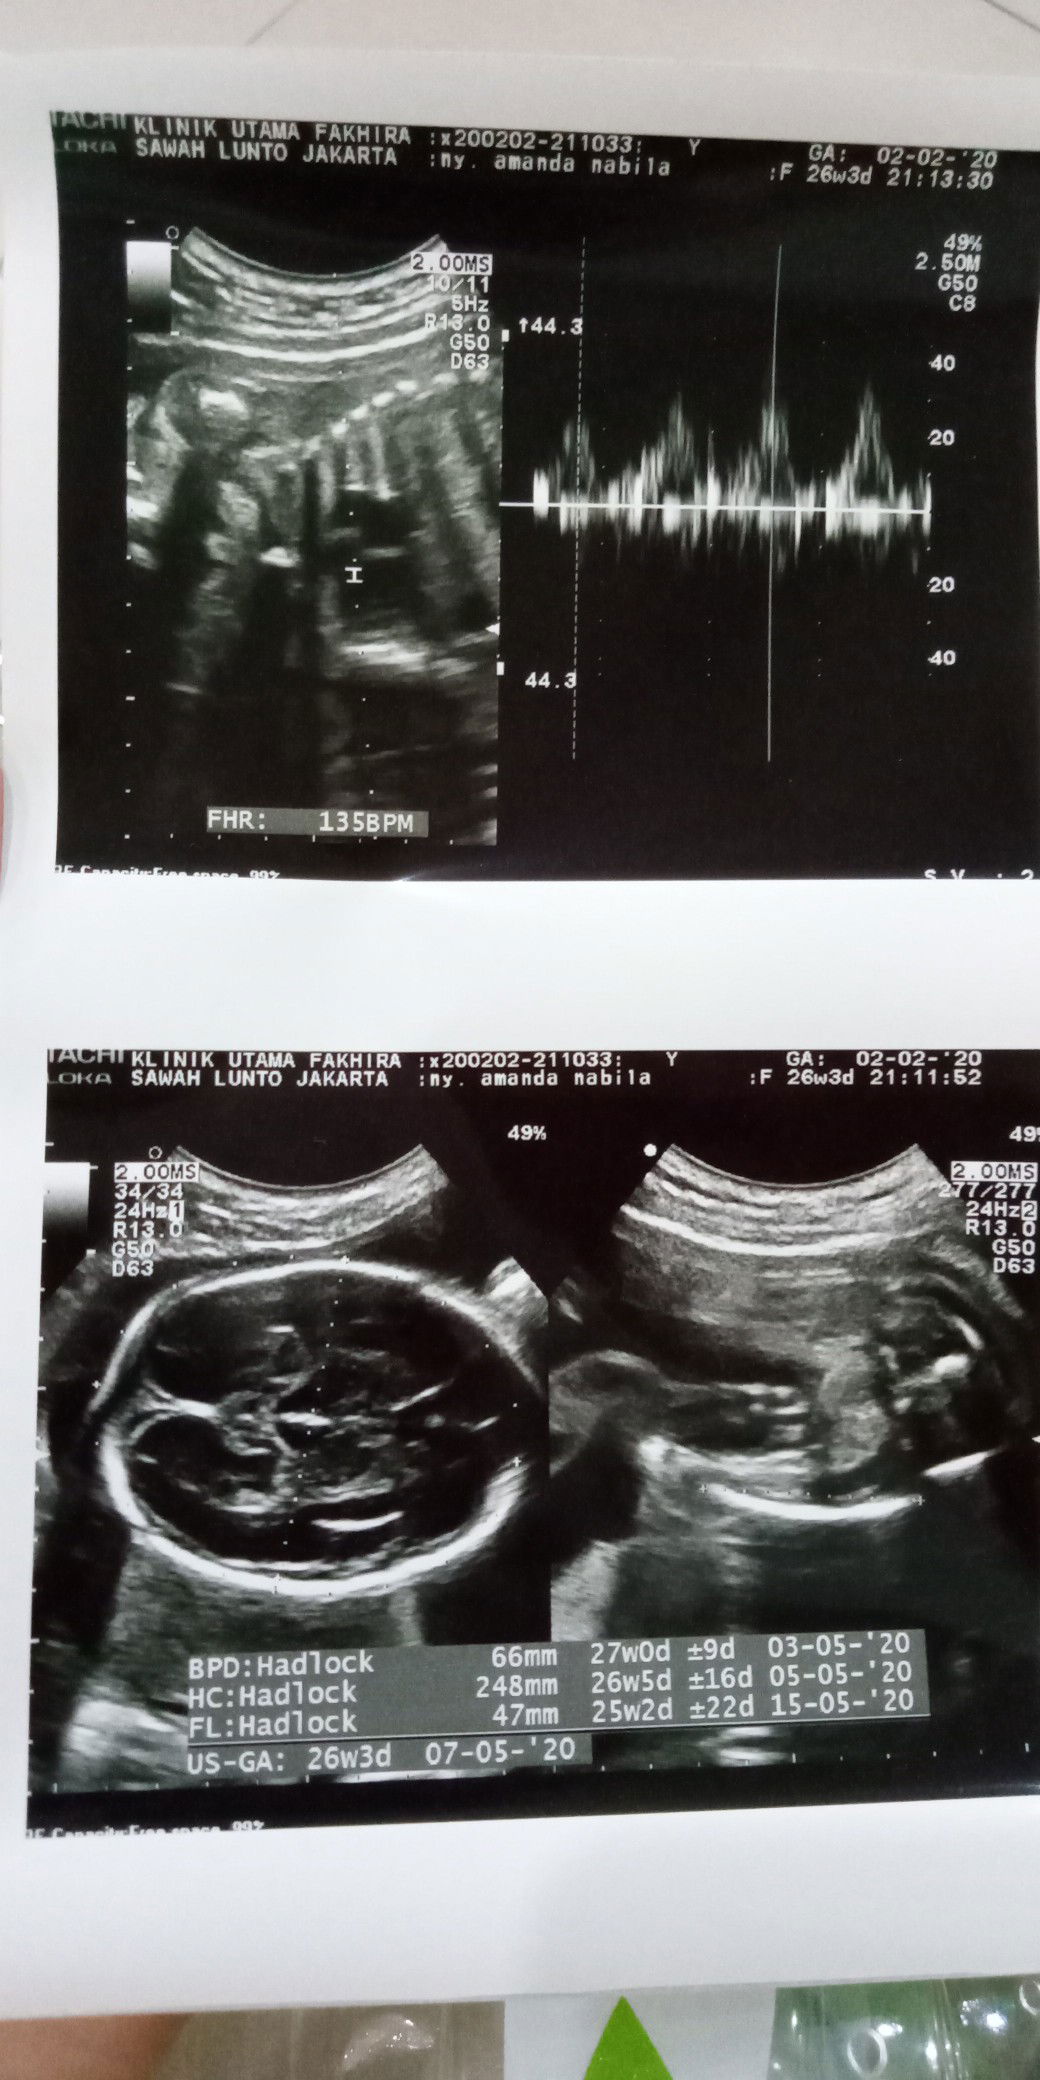

bbj janin

Hai bun.. aku habis nengokin si dd nih di usia 26w3d , jknya masih sama perkiraan laki2(dapet jagoan) hehe.. posisi kepala masih diatas ( masih bisa berubah katanya) letak pleseta juga Alhamdulillah ga nutupin jalan lahir.. bbj nya 957 Bun, kira2 normal atau lebih ya ??